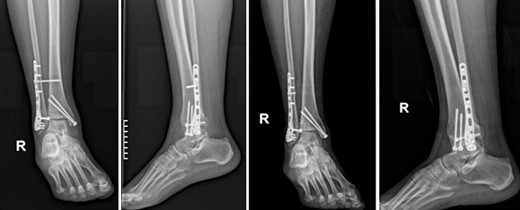

A surgical treatment was decided, consisting of ORIF of the fracture which was addressed within 48 hours of the admission to the hospital. Fracture reduction was achieved through a lateral and medial approach to the lateral and medial malleolar, respectively. A 3.5-mm neutralization plate with a lag screw was applied on the lateral malleolus combined with a 3.5-mm lag screw fixation of the medial malleolus and a 3.5-mm syndesmotic screw fixation (Fig. 2).

Postoperative anteroposterior and lateral X-ray of the ankle joint after ORIF of the fracture.